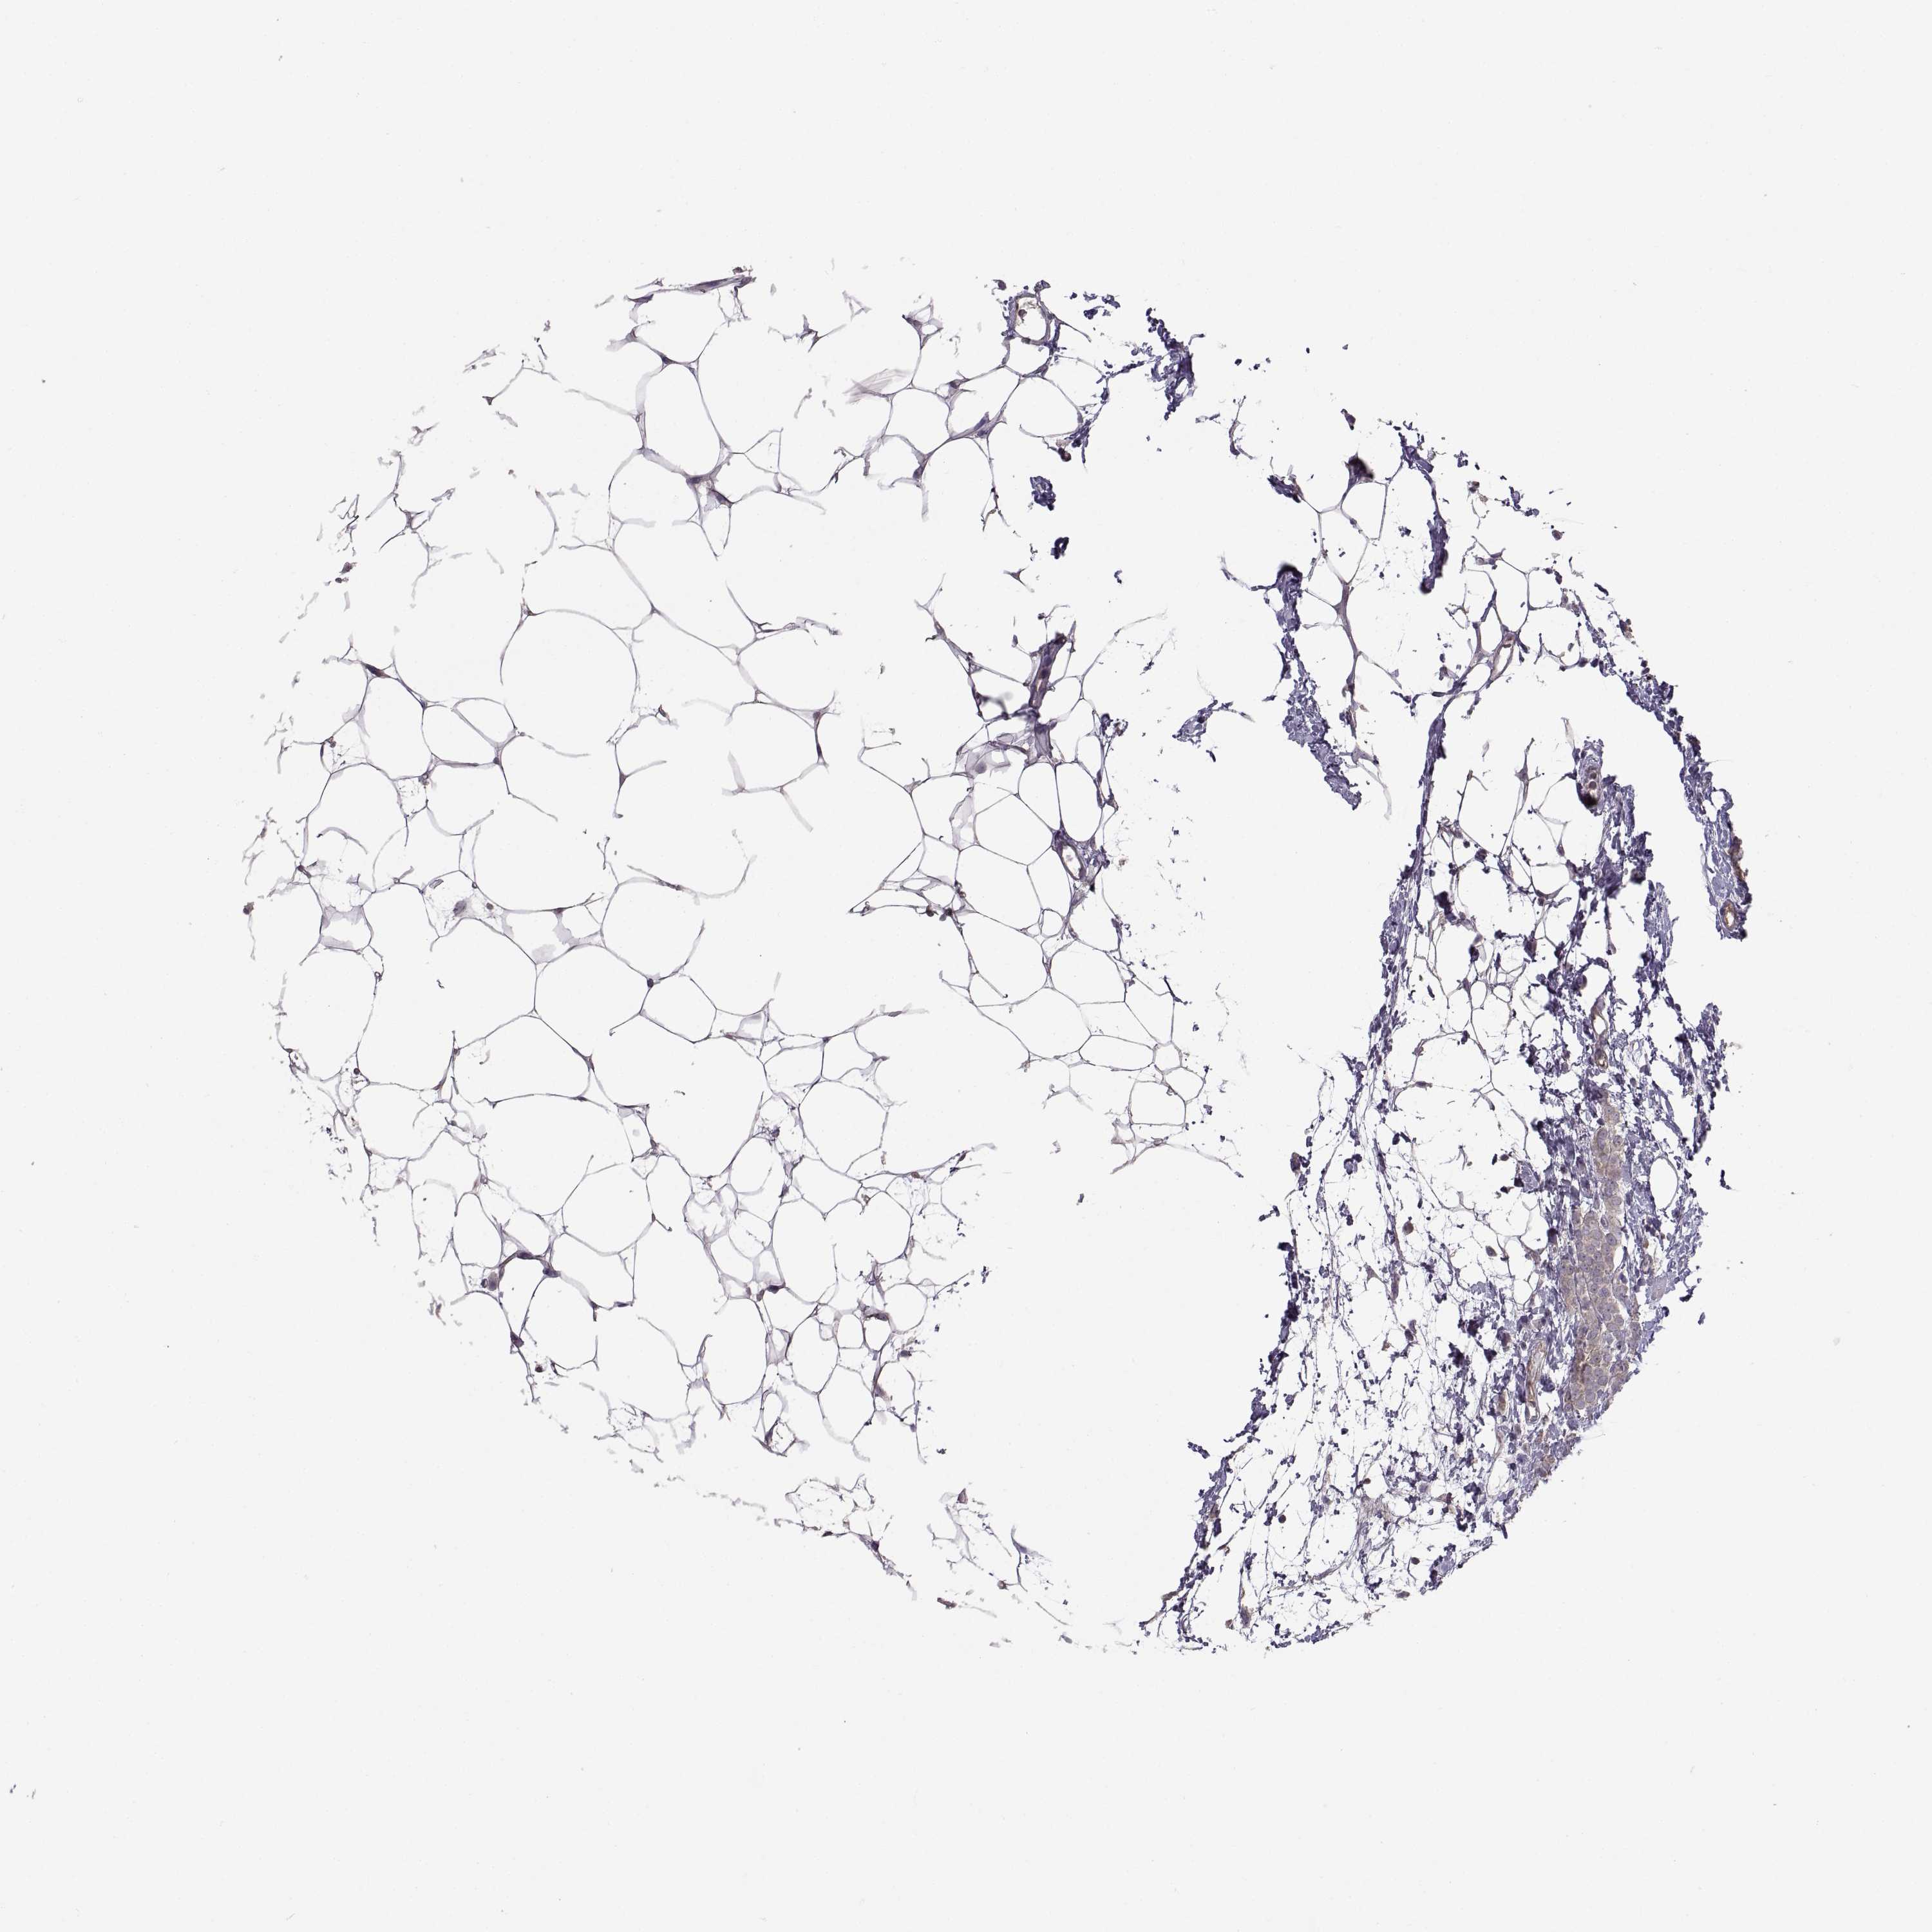

CANCER BREAST CANCER Show tissue menu

BRCA TCGA BRCA VALIDATION PROTEIN EXPRESSION

Breast cancer

Human cancer